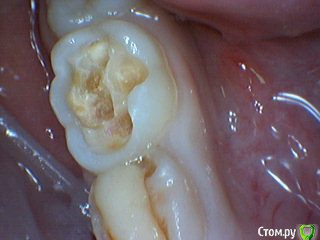

Давлетшин Опубликовано 15 мая, 2017 Поделиться Опубликовано 15 мая, 2017 (изменено) Есть такое слово НАДО. И надо делать ОПТГ в 6-7 лет. Здесь должна быть работа с рентгенологом. Можно отправлять снова и снова на снимки., пока не научится делать, с первого раза. Пусть рентгенолог объяснит позицию " чтобы не облучать". только цифрами и норм. актами. ну а потом и расстрелять можно, только не вы расстреливайте, а родители, за работу спрос с ВАС, а как вы можете сделать качественную диагностику и лечение без снимков. Вообще мне кажется на форуме, надо как то писать, когда задается вопрос, кто в каких условиях работает. может и более правильные рекомендации давали бы. Я дам одну рекомендацию. После 6-7 лет всех на ОПТГ. хоть за 100 км. через 15-20 ОПТГ пойдут"неожиданности" и еще больше укрепитесь в нужности исследования. На десерт неожиданность. Причем подозрение как то интуитивно вышло. Коментировать фото "какой я хороший/плохой, почему без кофера?" не буду. Скажу что был индикатор. И по вашему профилю ВЫ из Молдовы. интересно на одном ли языке мы говорим? Я про молочные премоляры. Мы в России то по разному думаем хотя программа в институтах одинаковая. Изменено 15 мая, 2017 пользователем Давлетшин 1 Ссылка на комментарий